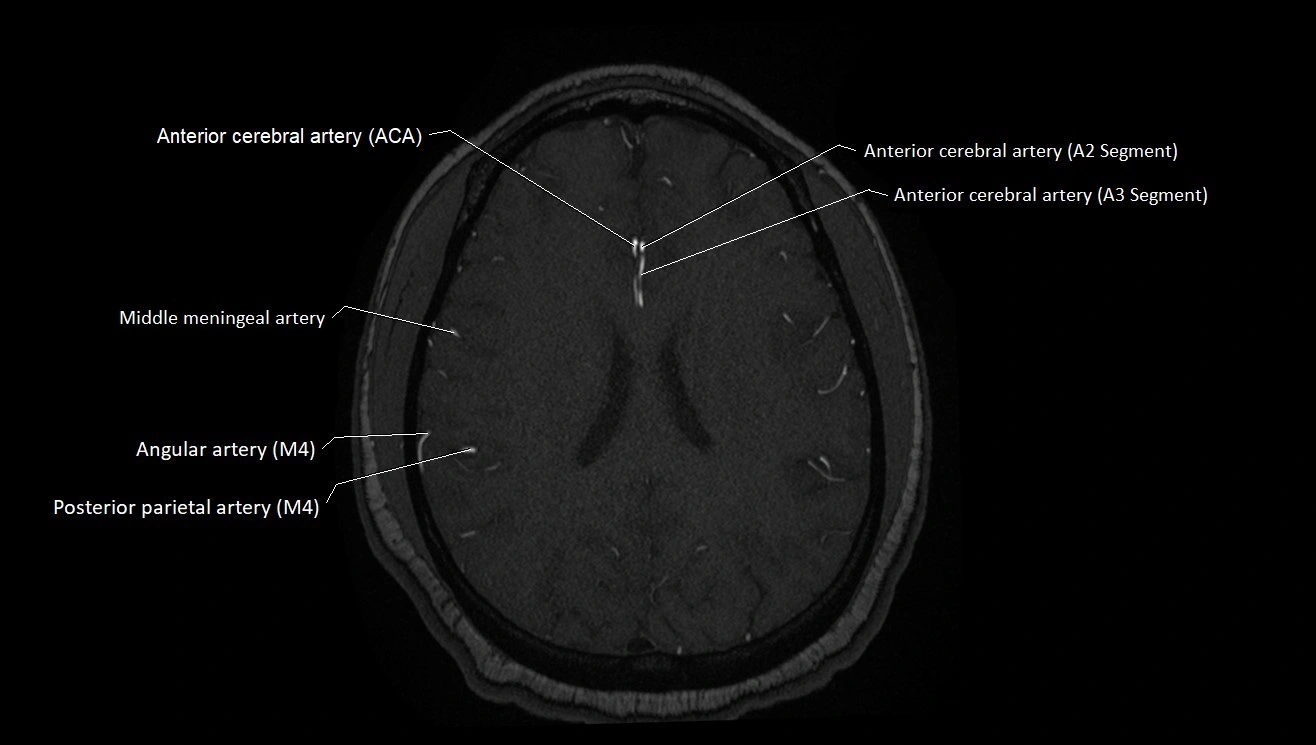

MRI images

image